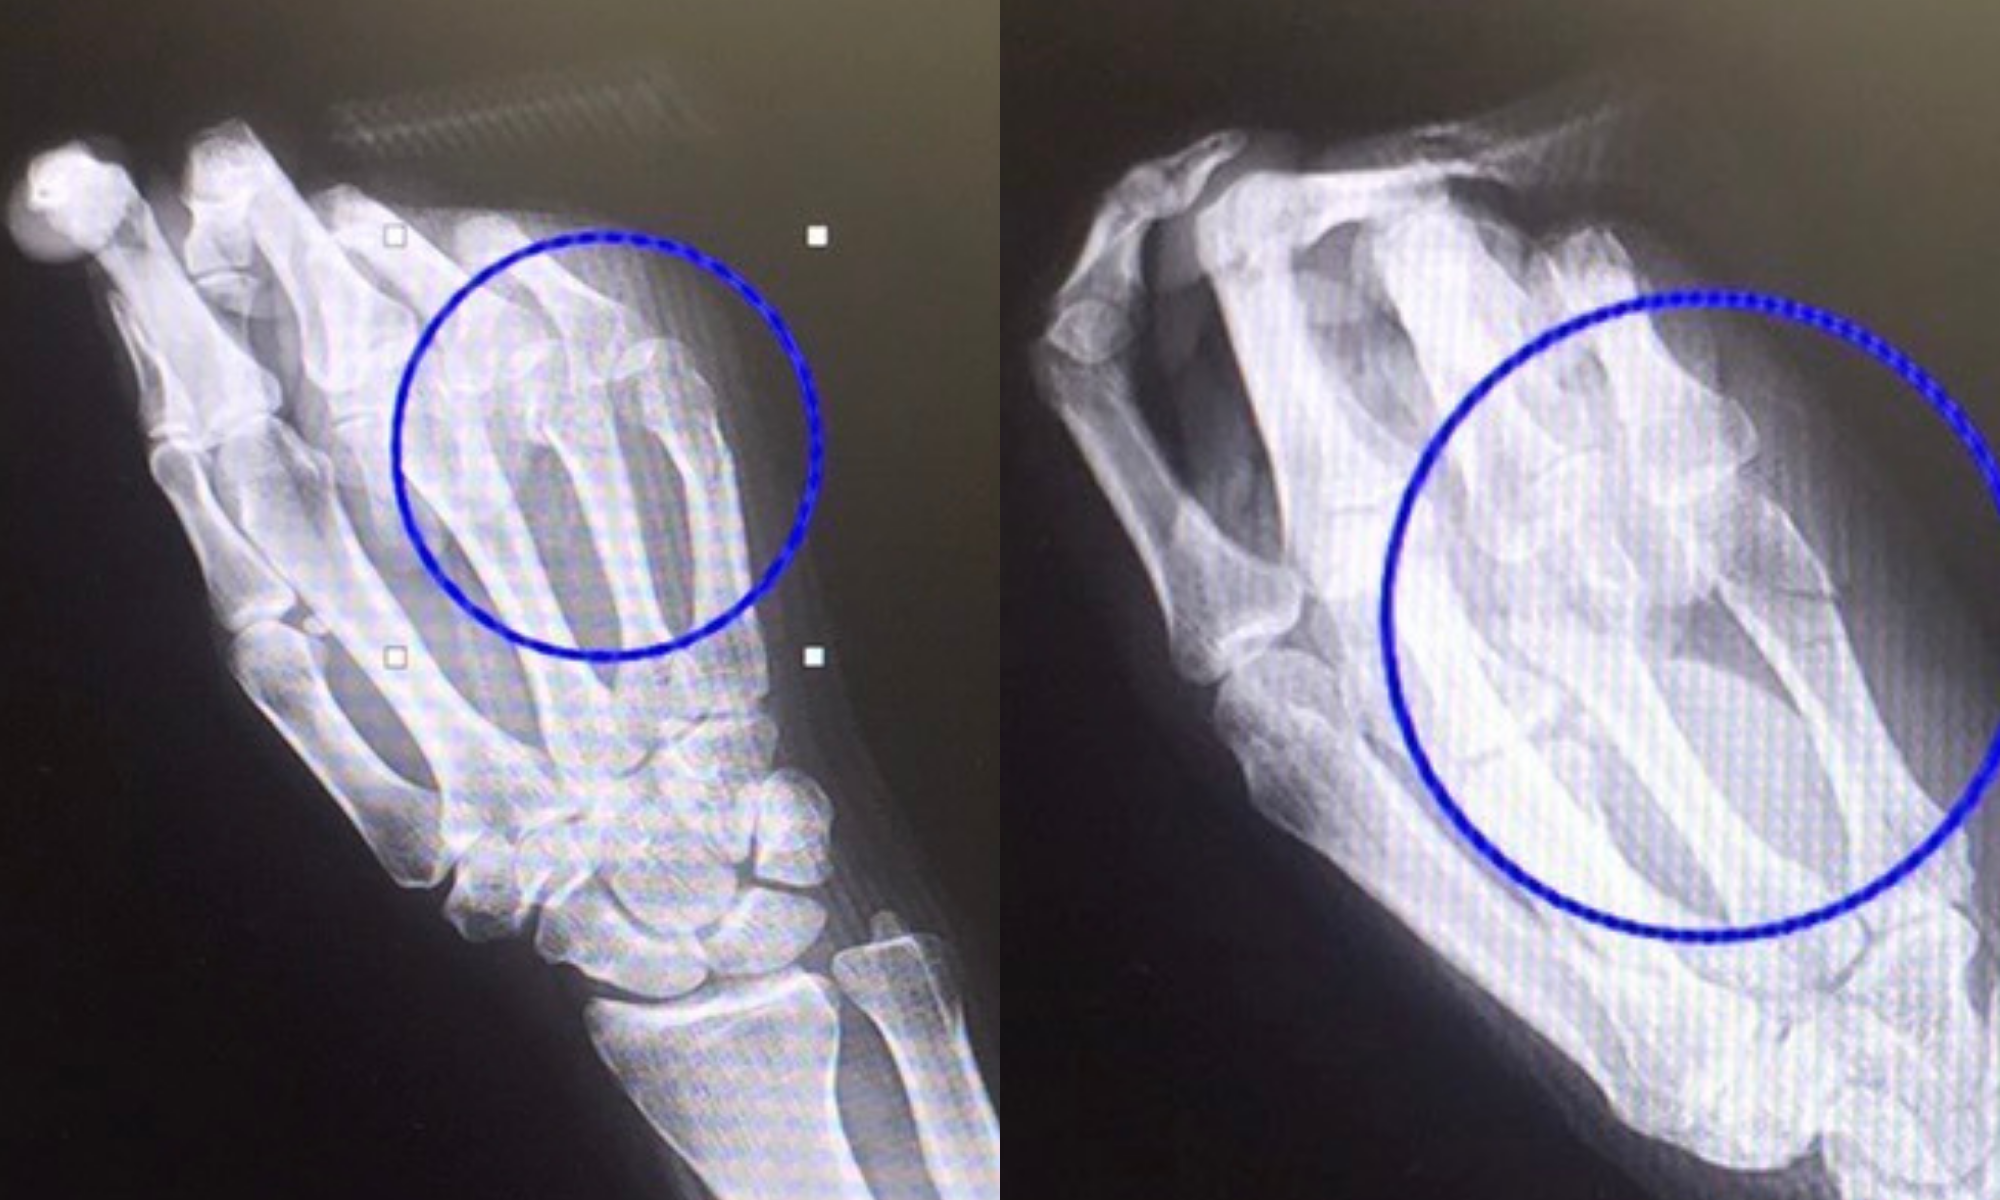

エコーでの整復前・整復後イメージ

整復の前後でエコー観察を行い、骨皮質の段差やアライメントの変化を確認しました。 画像で変化を確認できることは、固定肢位の妥当性や再転位リスクの説明にも役立ちます。